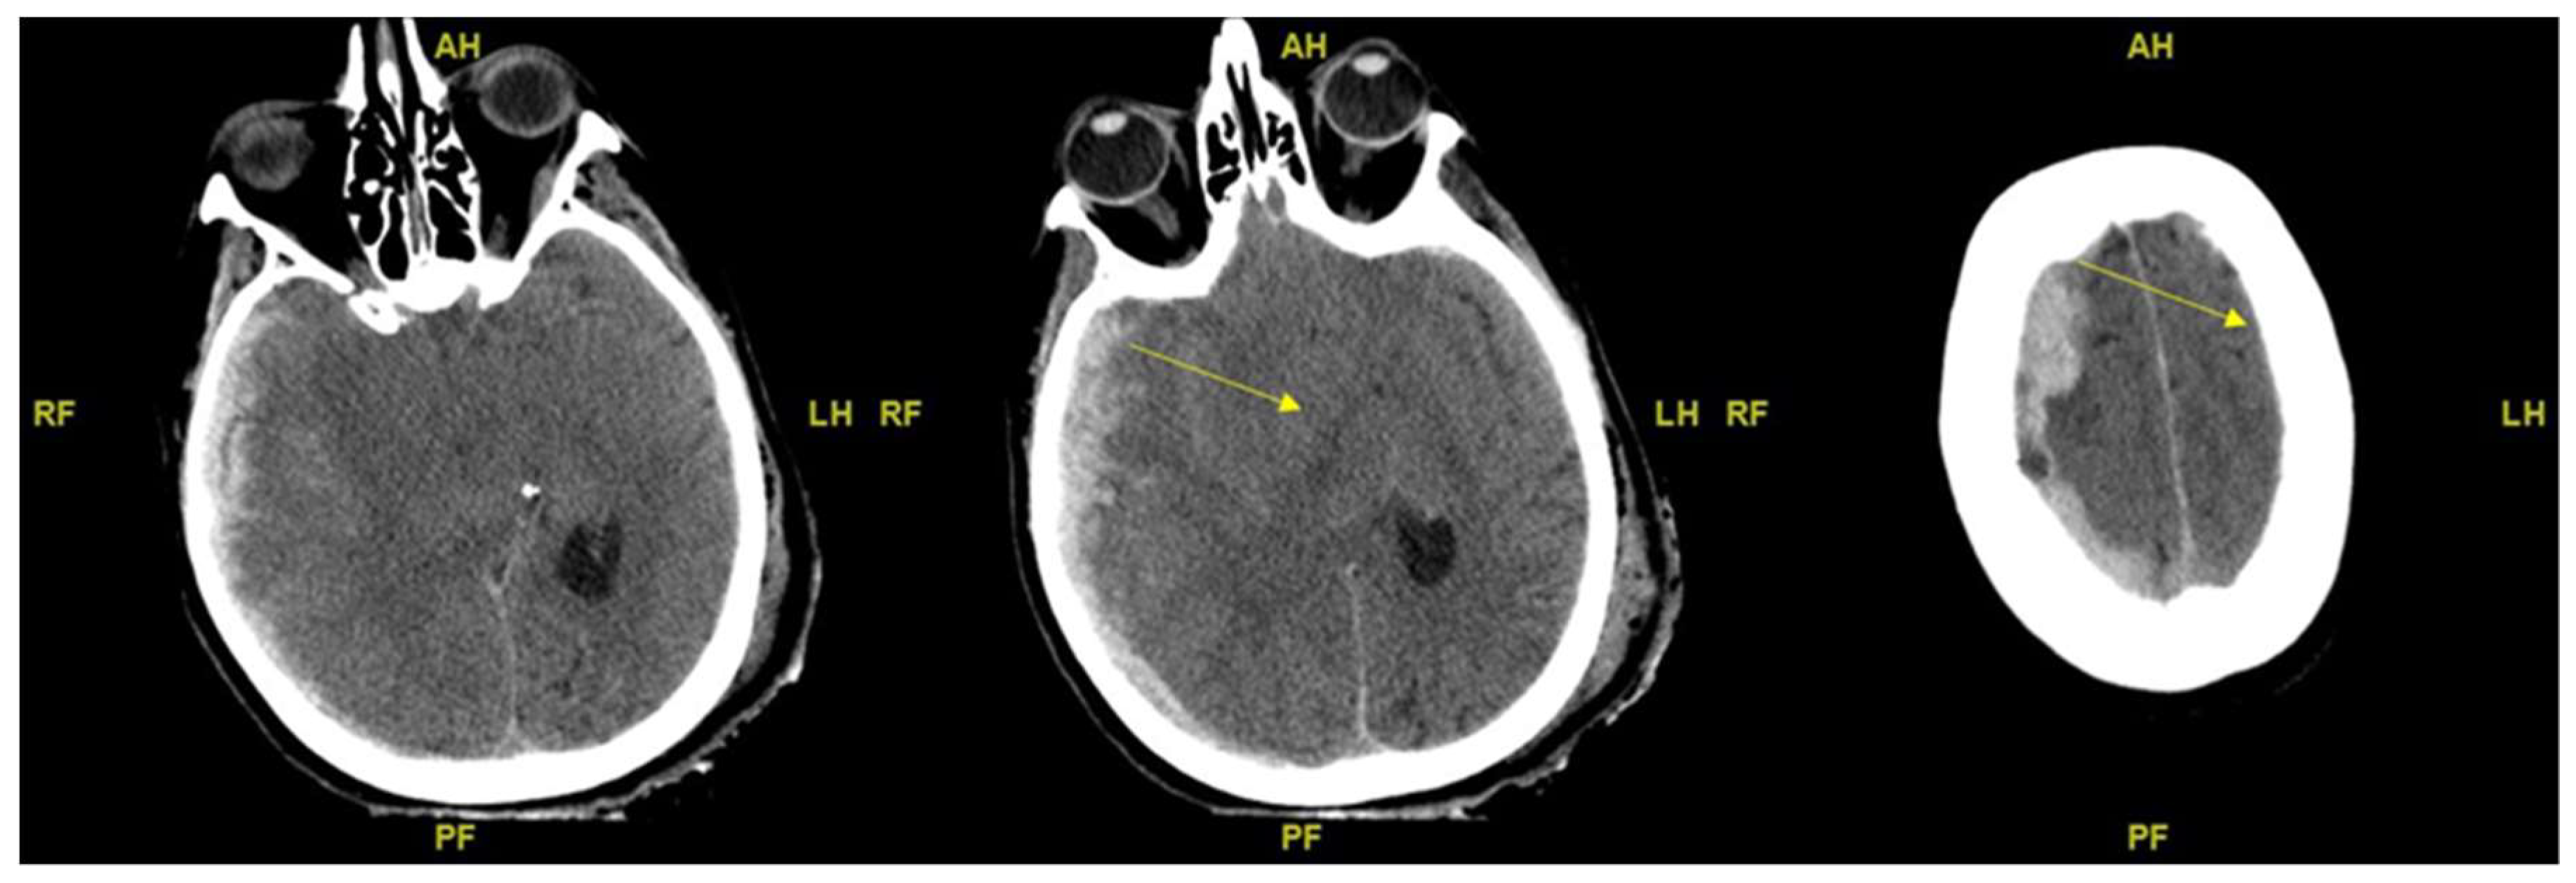

2.2. Evaluation of Brain Edema from CT Scans